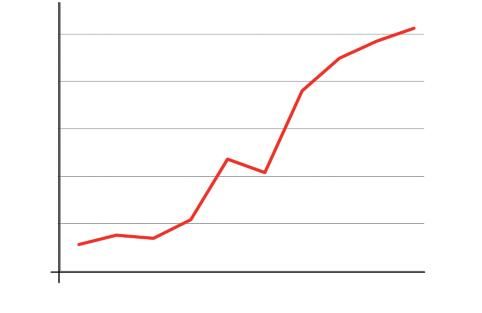

n. 2: l’incidenza del cancro è ancora in crescita

nonostante tutte le montature mediatiche sulle ‘scoperte’ mediche

Cosa significa ciò?

• Se una malattia si diffonde sempre di più, significa che i meccanismi di controllo non sono stati ancora scoperti o non vengono utilizzati nella pratica medica.

• Approcci tradizionali come la chemioterapia e la radioterapia, utilizzati su pazienti affetti da cancro per più di mezzo secolo, evidentemente non sono riusciti a frenare la diffusione del cancro.

• Quindi, la chemioterapia e le radiazioni non possono essere considerati una soluzione credibile per impedire la diffusione del cancro.

• Pertanto, vi è urgente bisogno di nuovi approcci efficaci per controllare la crescente diffusione del cancro!

Aumento del numero dei decessi dovuti al cancro nei diversi gruppi di età, dal 1970 al 2000

Età dei pazienti 70 - 79 anni

Età dei pazienti 60 - 69 anni

Età dei pazienti 50 - 59 anni

Dati statistici per gli USA, dati comparabili per l’Europa. Fonte: Journal of the American Medical Association, 2005